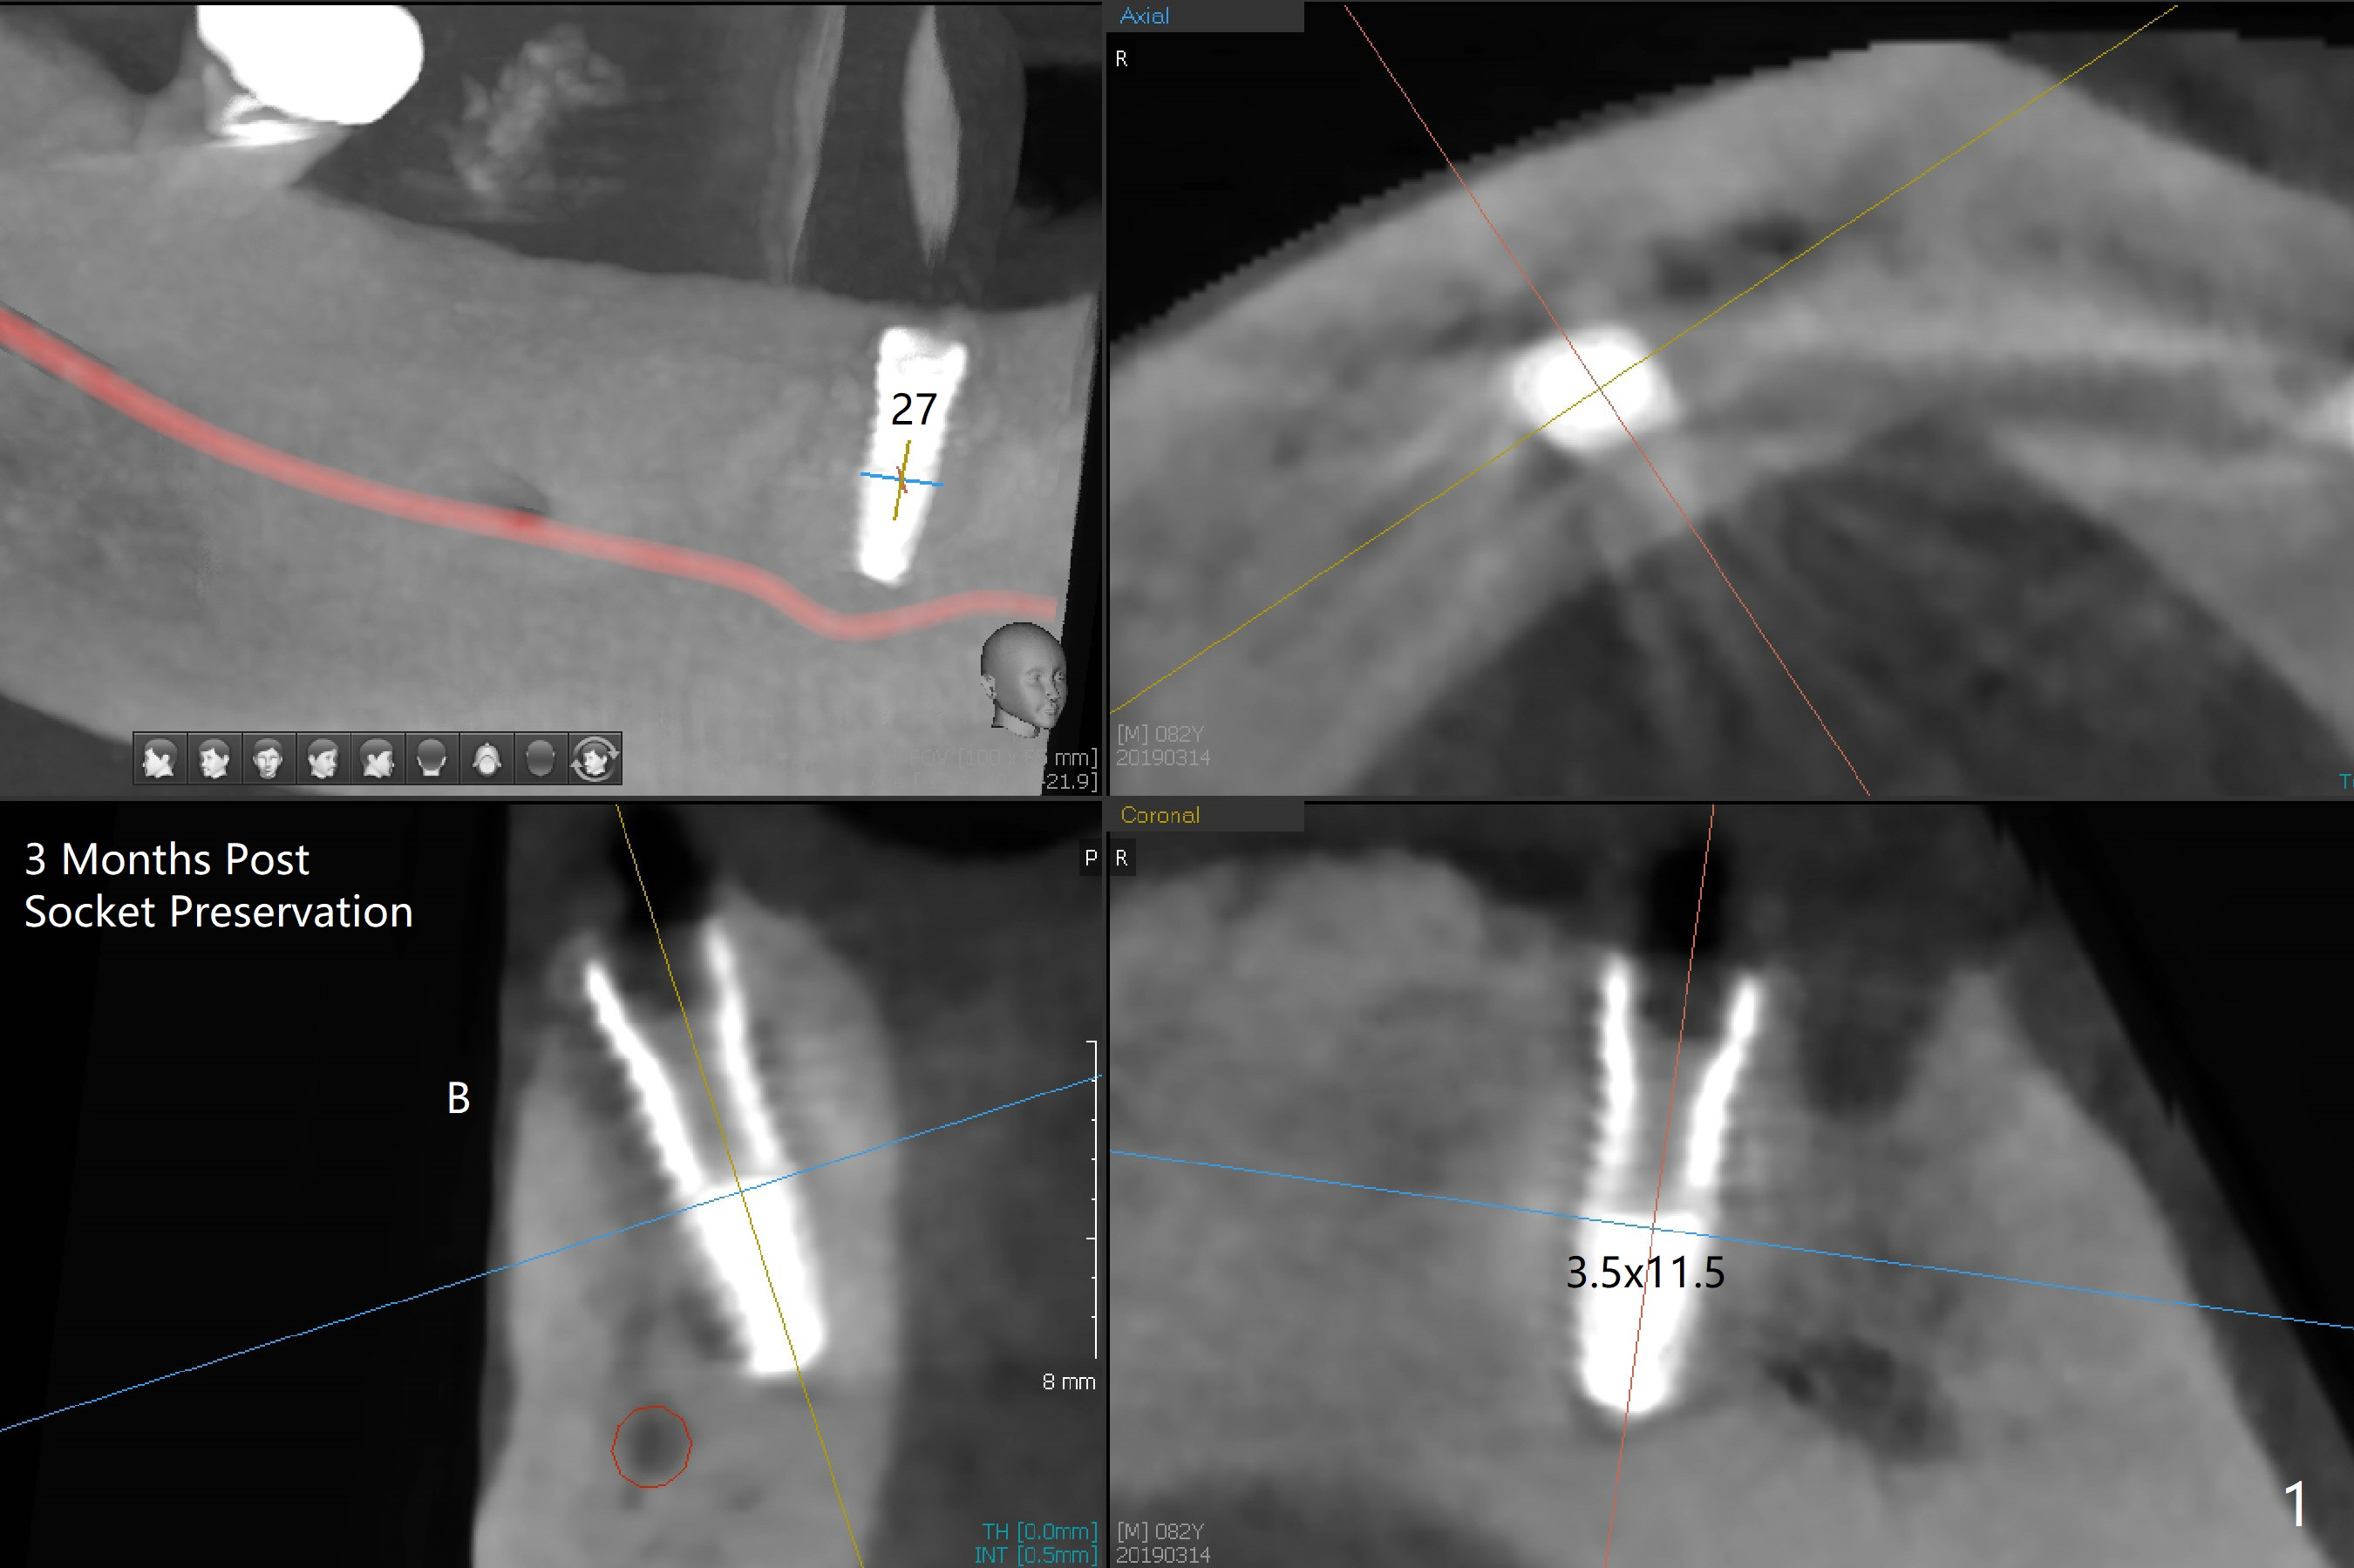

Three months post socket preservation (with buccal plate loss previously), a 3.5x11.5 mm implant is placed at #27 subcrestal (Fig.1). When implants are placed at #22 and 20 (Fig.2,4), threads are exposed buccal (B). Mixture of autogenous bone and allograft is placed to cover the exposed threads (Fig.3,5) following deep placement at #20. For safety, the implant at #20 is buried. Pain control at #18 is poor when initial osteotomy is being established (Fig.6 *), as related to severe infection. Repeated block anesthesia allows to finish implant placement with primary stability; a 3.5x2 mm ball abutment is placed (Fig.7). With placement of 2 other ball abutments at #27 and 22 (Fig.3), the lower existing RPD is converted to a removable provisional (Fig.8). With addition of acrylic, the socket of #20 is covered (Fig.9). There is no apparent bone #20 distal 3 months postop (Fig.10,11 <). Re-graft is needed? The implant at #21 appears immediately subgingival 5 months postop (Fig.12 *). The distobuccal threads are exposed (Fig.13). After decortication, allograft is placed, followed by 6-month membrane. In fact, a shorter and smaller implant should be placed instead. The patient has to wear the RPD for mastication. It would be more painful without it. Later the tissue surface of the RPD is trimmed.